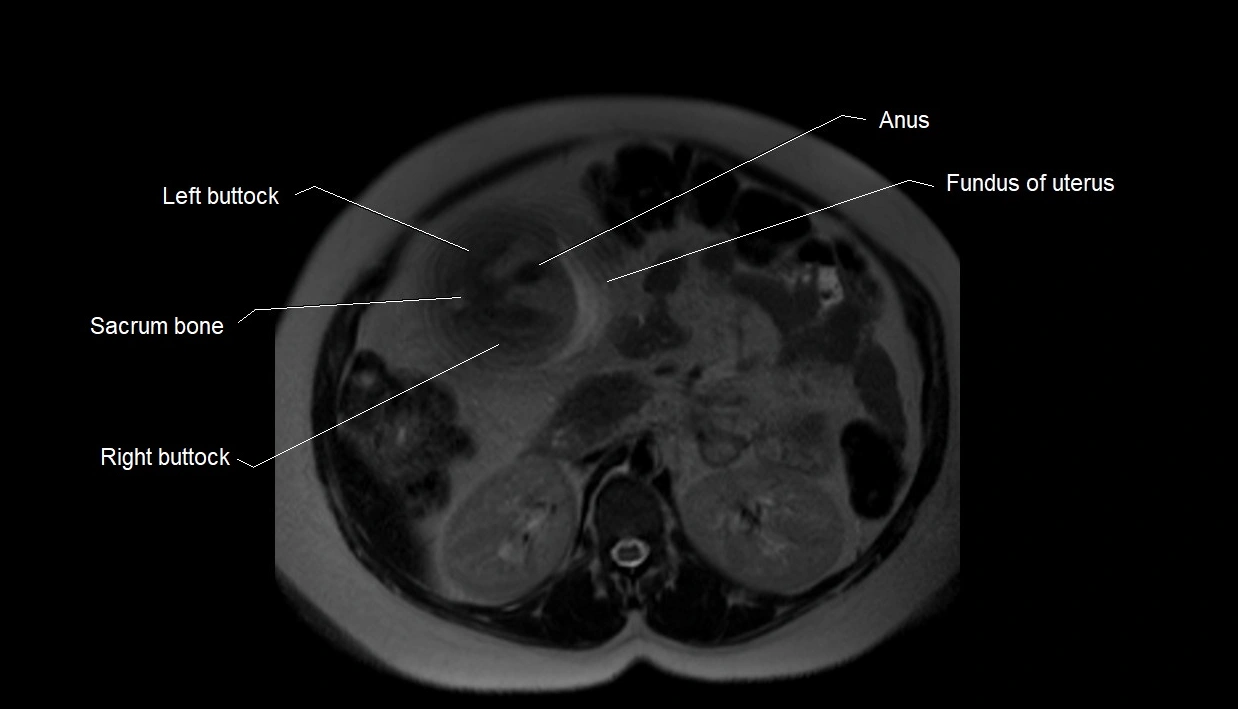

MRI Appearance

T2 HASTE (T2 GRE):

• Amniotic fluid shows very bright hyperintense signal

• Provides natural contrast against fetus and placenta

• Small particles (vernix) may appear as scattered hypointense foci within bright fluid

T1 GRE:

• Amniotic fluid shows low signal intensity (dark)

• Hemorrhage, infection, or proteinaceous content may cause focal or diffuse high signal intensity

MRI image

image